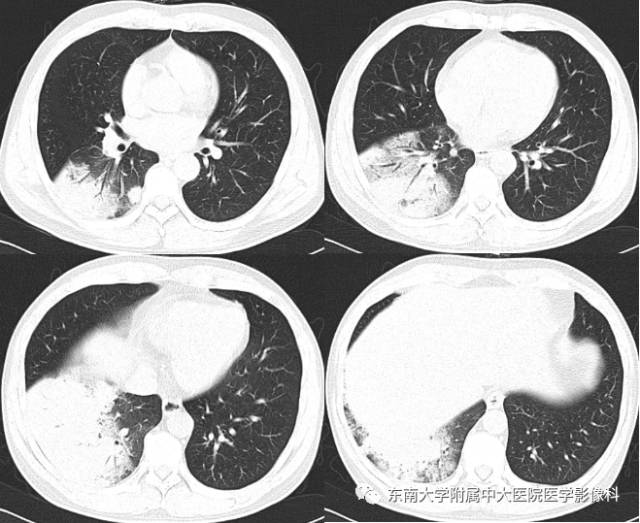

2015-10-27 抗感染治疗后复查